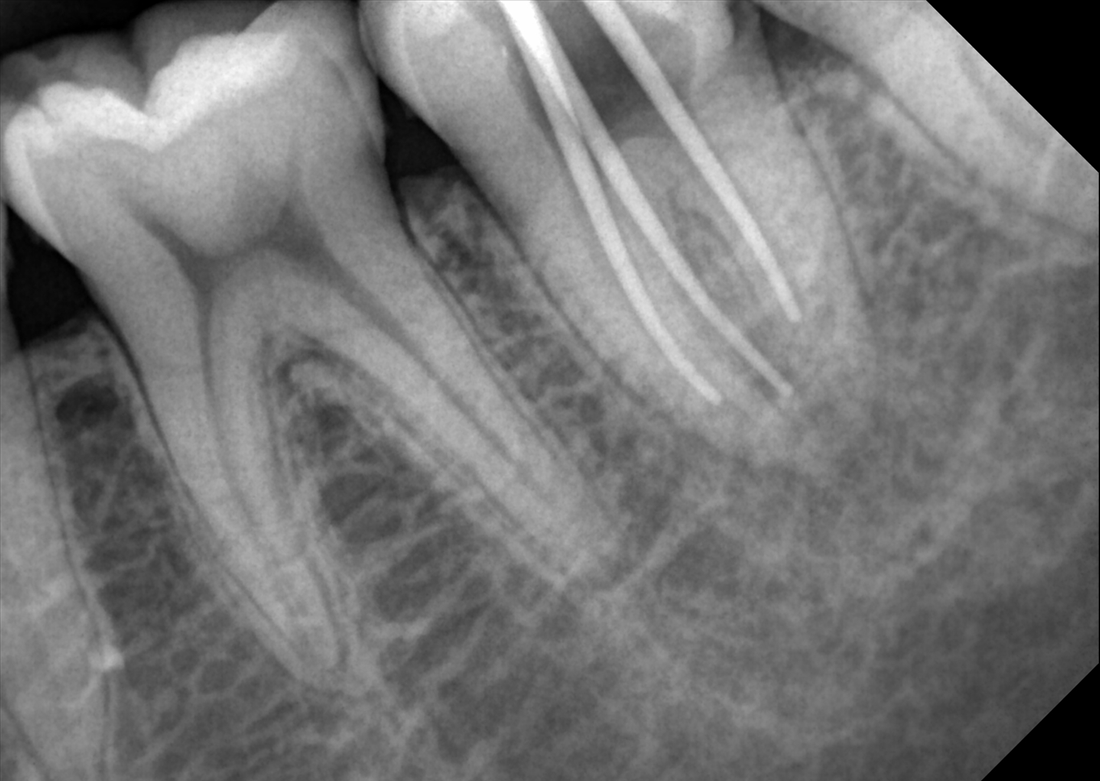

KLİNİK FOTOĞRAFLAR

Firmanın uzun yıllara dayanan dental görüntüleme tecrübesi ile son teknoloji sensor reseptörleri kullanılarak üretilmiştir ve görüntü kalitesi mükemmel düzeydedir.